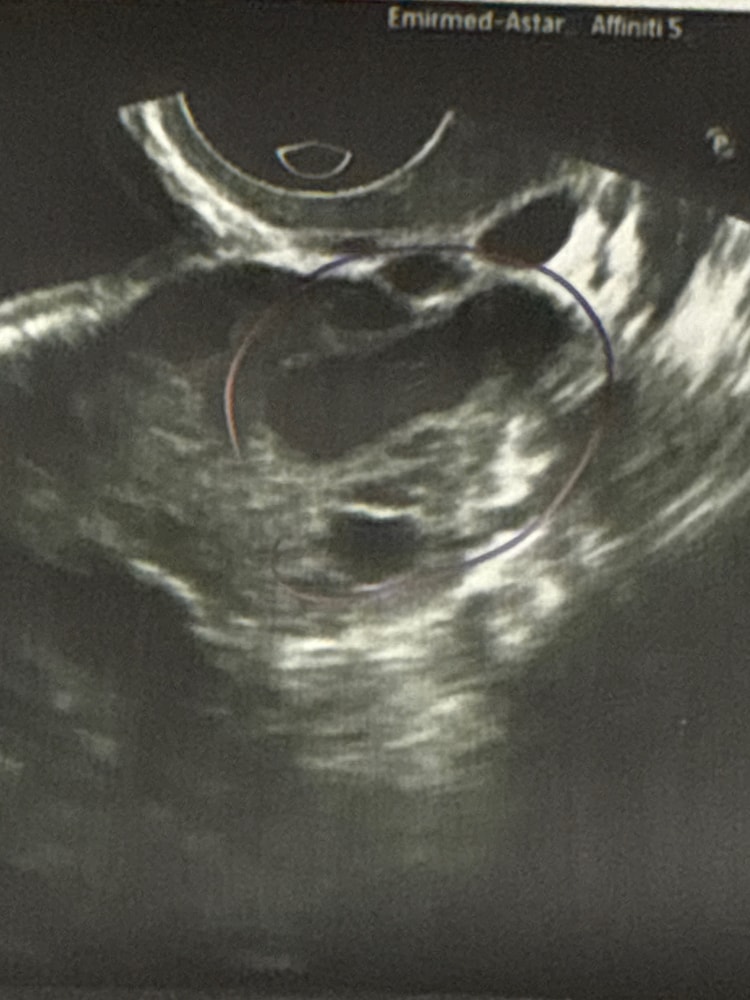

УЗИ на 30 день цикла

Сбегала на УЗИ, беспокоит боль в промежности и вот решила взглянуть и пойти с УЗИ к гинекологу.

желтое тело 16мм с хорошим кровотоком и это при том, что была подтвержденная овуляция еще 01 февраля. Тесты все пустые. Задержка.

что думать - не знаю. ХГЧ сдам, но на 30дц думаю тесты уже бы п